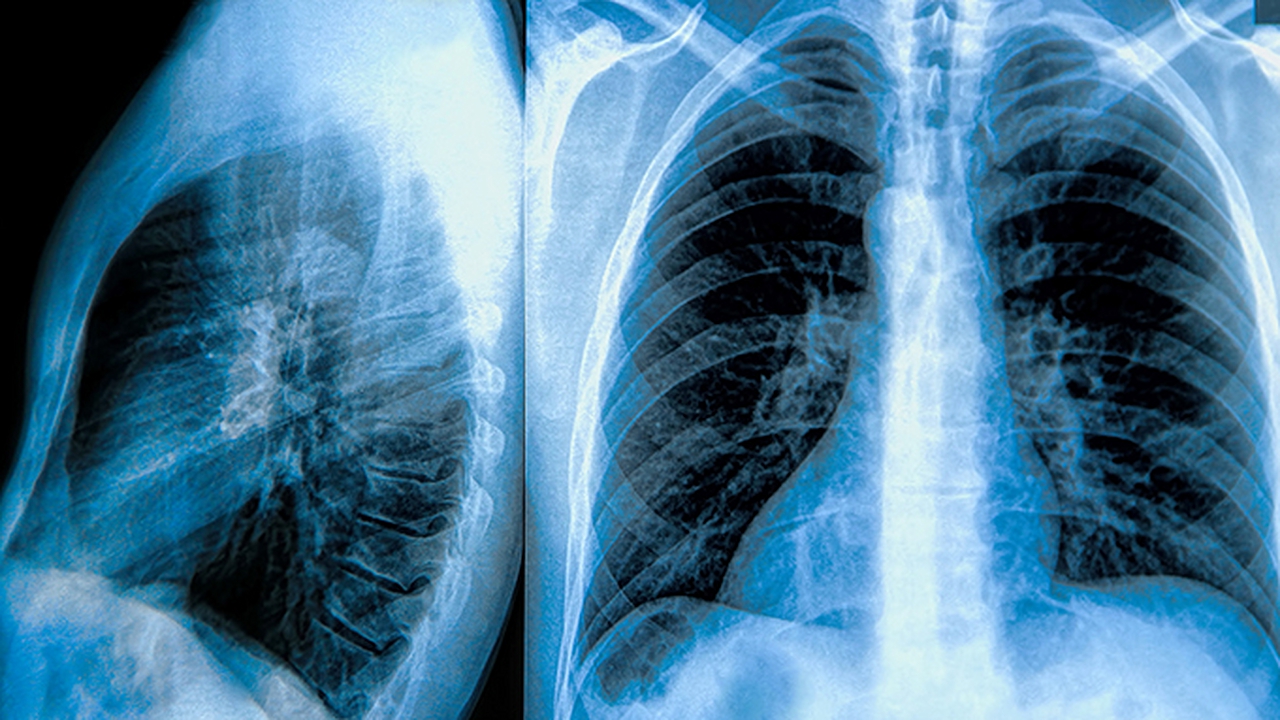

肺部疾病是常见的呼吸系统疾病,包括肺炎、慢性阻塞性肺疾病、肺结核、肺癌等。这些疾病的发病原因复杂,可能与感染、环境污染、吸烟、遗传等因素有关。及时到专业医院就诊对肺部疾病的治疗至关重要。

成都中医哮喘医院·成都中医肺科医院坐落于成都市金牛区金科东路29号,建筑面积近15000㎡。是经金牛区卫计局批准成立的以诊治胸、肺、呼吸系统疾病为主的国家二级专科医院。医院现已集结了一批国内外医疗专家,组建起涵盖呼吸与危重症医学科、胸外科、检验科、影像科、病理科的多学科专家团队,为诊疗提供全方位支撑。在积极推进学科、人才建设,打造医院“软”实力的同时,医院还引进了一系列的医疗设备设施,不断夯实“硬”实力,包括胸腔镜微创技术、联影64排16层螺旋CT、联影数字放射成像系统(DR)、NSA800全自动生化分析系统、呼出气一氧化氮(FeNO)测定、超导可视支气管镜介入技术、TTS动力温控技术,肺部气道喷注、肺结节冷冻消融术等。